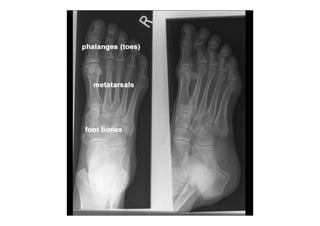

RADIOLOGIA DO

TRAUMA DO ESQUELETO

Referência: http://www.accessexcellence.org/RC/VL/